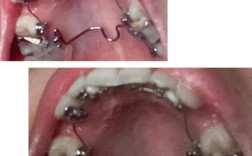

在正畸治疗中,TPA(Transpalatal Arch,横腭杆)是一种常用的辅助装置,主要由不锈钢丝制成,形态呈“U”形或“N”形,两端通过焊接或粘接的方式固定在上下颌第一磨牙的带环或托槽上,横跨硬腭中部连接两侧后牙,其设计简单却功能多样,在牙齿移动、支抗控制、牙弓形态维持等方面发挥着不可替代的作用,尤其在复杂错颌畸形的治疗中,常作为正畸医生的重要“工具”之一。

增强支抗控制,稳定后牙位置

支抗控制是正畸治疗的关键,指在移动目标牙齿时,尽可能保持其他牙齿(尤其是后牙)的稳定,避免不必要的移动,TPA通过连接两侧第一磨牙,将后牙区形成一个“整体支抗单位”,当需要内收前牙(如拔牙病例中关闭拔牙间隙)时,TPA能有效抵抗前牙移动时产生的反作用力,防止后牙前移,确保支抗牙的稳定性,在拔除上下颌第一前磨牙的病例中,若不使用支抗装置,前牙内收时后牙可能前移2-3mm,导致磨牙关系改变、面型恶化;而TPA通过腭部的刚性连接,将后牙前移量控制在0.5mm以内,为前牙精确移动提供可靠支抗,TPA还可用于“颌间支抗”,配合颌间牵引(如Ⅲ类牵引)时,通过稳定后牙,增强牵引力的传递效率,避免后牙咬合干扰。